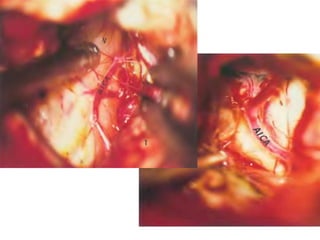

Right sided anterior petrosectomy on a cadaver dissection: intradural exposure

and operative field. PCA Petrous carotid artery; DPA drilled petrous apex; IPS

inferior petrosal sinus; BA basilar artery; VI 6th cranial nerve; AICA anterior inferior

cerebellar artery; P pons; V 5th cranial nerve